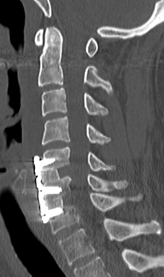

頚椎OPLLを認め脊髄を圧迫している状態です。前方からの骨化浮上術により症状は改善しています。